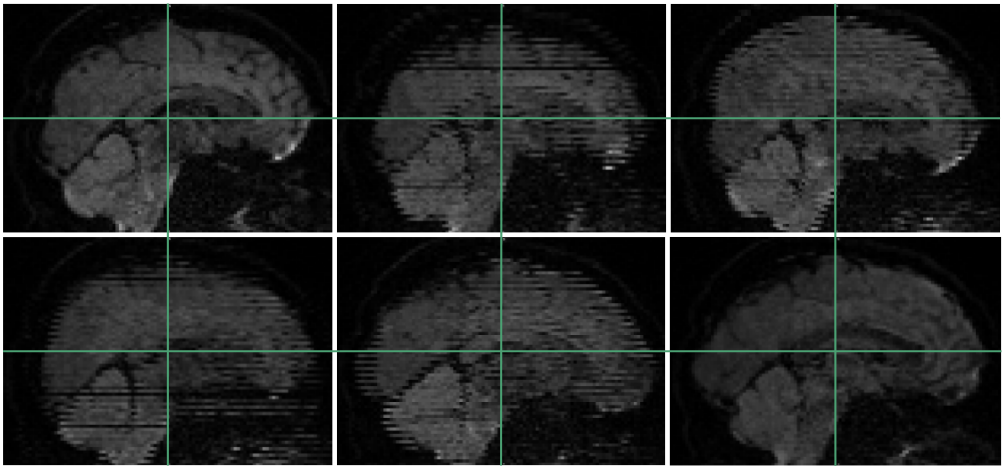

From these datasets, we use the five non-diffusion weighted () MRI scans each, as well as 30 diffusion weighted images (, diffusion gradient duration , spacing ). Each image consists of voxels with a resolution of . The data, and the effects of subject motion, are illustrated in Figure 6.

It can be seen in Figure 6 that subject motion during different phases of the acquisition leads to different types of artifacts. Results in Table 1 include the motion correction described in Section 3.3, which compensates spatial misalignments of different scans. However, motion can also lead to signal dropouts or to distortions within scans, which our current codec does not explicitly account for. This explains why q-space inpainting is less effective on the second as compared to the first scan. However, even on this challenging dataset that exhibits unusually strong artifacts, q-space inpainting still provides a benefit compared to all other alternatives.